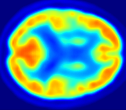

4.0.2 Qualitative Results

Looking at sample synthetic PET images in Fig. 3, it can be seen that all of the models are able to make reasonable predictions. The outputs of the U-PET and U-PET (no att.) look very similar and are smoothed compared to the input. The pix2pix predicts more details, which seem to be important for the discriminator. However, even though this model has finer predictions, the intensity values are worse compared to the U-PET and U-PET (no att.) as seen in Fig. 2; an example is given in Fig. 3 in the second row.

From a clinical perspective, the synthetic generated PET show a smoother version of the real PET images but keep the same pattern of FDG uptake, especially, hypometabolism in the respective brain areas. This backs up our hypothesis, that MRI contains information that correlates with the functional information of PET images. Moreover, the synthetic PET could be used as complementary visualization for physicians beyond the task of classification.

In Fig. 4, the attention maps of the U-PET are shown for multiple examples. On the one hand, the attention map of the skip connection (AttMap skip) highlights details of the brain structure, which is in agreement with the assumption that the network has to transform the specific structures of the MRI scan into the PET modality. On the other hand, the attention gates used for the classification task rather focus on more specific regions. One can observe a trend that the attention maps used for classification tend to highlight regions which have a low uptake in the PET. Since areas with a lower uptake in the PET correspond to areas with lower functional activity (hypometabolism), this focus area of the network seems reasonable with respect to the classification task.